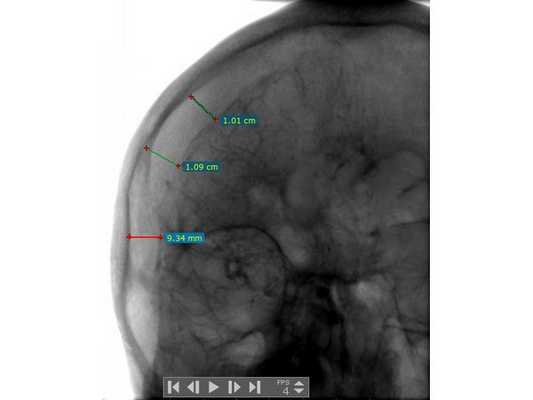

Анализ крови на алкоголь — 0 промилле. Выполнена диагностическая люмбальная пункция, выявлено субарахноидальное кровоизлияние: 10-15 эритроцитов в поле зрения. При помощи эхоэнцефалоскопии обнаружено смещение срединных структур головного мозга на 3-4 мм влево. Т.е. у пациента имеются клинические данные, указывающие на внутричерепную гематому справа, но при отсутствии КТ/МРТ-диагностики определить её объём и локализацию сложно. Для дальнейшего диагностического поиска пациенту выполнена церебральная ангиография. На ангиограммах отмечено отжатие сосудистой сети правого полушария головного мозга от костей свода черепа почти на 10 мм (рис. 1). В левом полушарии патологии не выявлено (рис. 2).

Пациент взят на операцию: ⠀•⠀Выполнен дугообразный разрез мягких тканей в правой лобно-височно-теменной области. Скелетирована кость. ⠀•⠀Наложены два фрезевых отверстия, из которых краниотомом выпилен костный лоскут 6,0*8,0 см. ⠀•⠀Произведён гемостаз моно- и биполярной коагуляцией, воском по ходу доступа. ⠀•⠀Твёрдая мозговая оболочка вскрыта подковообразно. Визуализирована субдуральная гематома, представленная плотными сгустками тёмно-вишнёвого цвета (рис. 3). ⠀•⠀Начато удаление сгустков путём аспирации и отмыванием физиологическим раствором. Общий объём субдуральной гематомы около 120 мл. Признаков черепно-мозговой травмы (кортикальных очагов ушиба, травматического субарахноидального кровоизлияния, гиперемии, отёка головного мозга) нет. ⠀•⠀При удалении сгустков с конвекситальной поверхности лобной доли открылось интенсивное венозное кровотечение. С целью доступа к источнику кровотечения разрез мягких тканей продолжен в конвекситальном направлении и краниотомом выпилены два дополнительных костных лоскута (из-за интенсивности кровотечения найти локализацию источника было затруднительно). ⠀•⠀Визуализировано кровоточащее образование, сращённое с твёрдой мозговой оболочкой и корой головного мозга, по виду — сосудистая мальформация (рис. 4). ⠀•⠀Гемостаз подходящих сосудов и самого образования выполнен последовательной биполярной коагуляцией (рис. 5: сосудистая мальформация указана наконечником аспиратора). ⠀•⠀Кровотечение остановлено. Мозг расправился, пульсирует. Твёрдая мозговая оболочка ушита викрилом с одновременным подшиванием по периметру трепанационного окна (рис. 6). ⠀•⠀Дефекты твёрдой мозговой оболочки и сосудистая мальформация укрыты гемостатической губкой (рис. 7). ⠀•⠀Костные лоскуты уложены на место (рис. 8). ⠀•⠀Послойный шов раны выполнен викрилом и капроном. ⠀•⠀Кожа ушита обвивным швом по Мультановскому. Ретроспективно на фронтальной ангиограмме можно заподозрить сосудистую мальформацию, ставшую источником гематомы (рис. 9). На девятые сутки после операции для обеспечения проходимости дыхательных путей, проведения длительной искусственной вентиляции лёгких, облегчения санации трахеи и бронхов пациенту выполнена нижняя трахеостомия по Бьёрку.